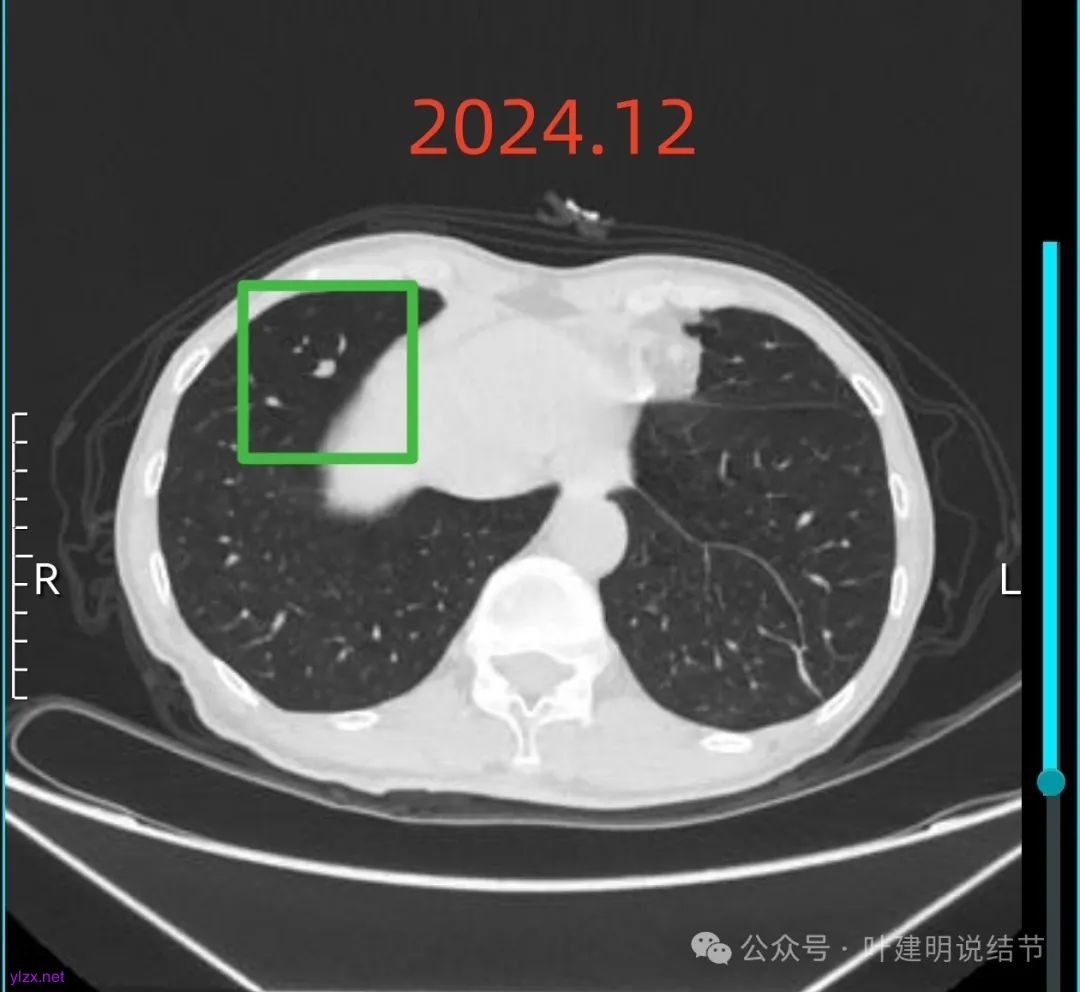

再来看2024年12月时的影像:

右下实性结节两年来没有变化,那它就是良性的可能性大些了,至少目前不考虑干预处理。

右上混合阴影也没有明显进展,则同样要更倾向确实是支气管扩张伴慢性炎与纤维增生的关系,可随访。